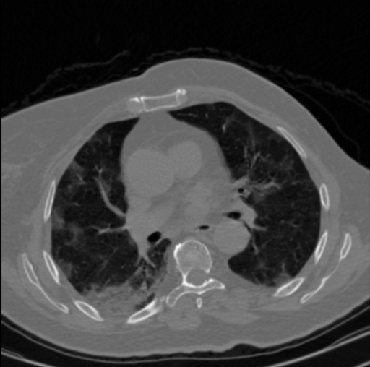

Early and reliable COVID-19 diagnosis based on chest 3-D CT scans can assist medical specialists in vital circumstances. Deep learning methodologies constitute a main approach for chest CT scan analysis and disease prediction. However, large annotated databases are necessary for developing deep learning models that are able to provide COVID-19 diagnosis across various medical environments in different countries. Due to privacy issues, publicly available COVID-19 CT datasets are highly difficult to obtain, which hinders the research and development of AI-enabled diagnosis methods of COVID-19 based on CT scans. In this paper we present the COV19-CT-DB database which is annotated for COVID-19, consisting of about 5,000 3-D CT scans, We have split the database in training, validation and test datasets. The former two datasets can be used for training and validation of machine learning models, while the latter will be used for evaluation of the developed models. We also present a deep learning approach, based on a CNN-RNN network and report its performance on the COVID19-CT-DB database.